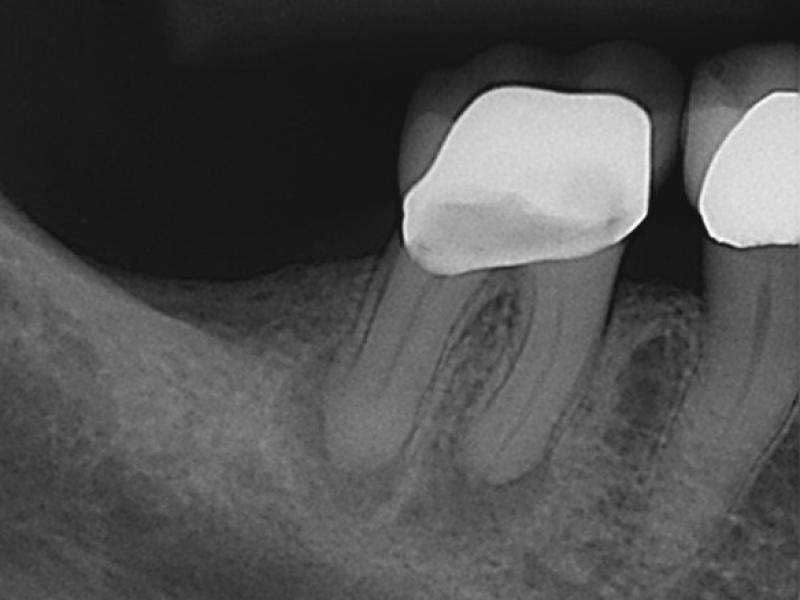

Pre-Op